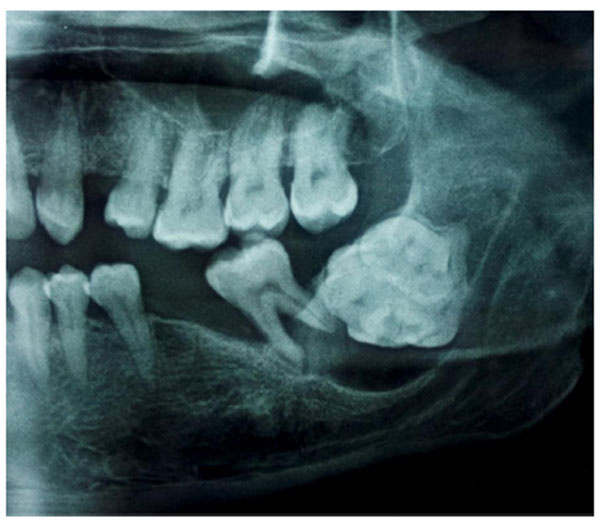

7. Изменения на рентгенограмме. На рентгеновском снимке одонтома выглядит как четко очерченное образование с различной степенью минерализации.

· Ортопантомограмма (ОПТГ) – панорамный снимок обеих челюстей, который позволяет оценить состояние всей зубочелюстной системы. ОПТГ помогает выявить локализацию, размеры и структуру одонтомы.